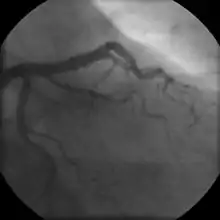

- Coronary angiography

In "stable" angina, chest pain with typical features occurring at predictable levels of exertion, various forms of cardiac stress tests may be used to induce both symptoms and detect changes by way of electrocardiography (using an ECG), echocardiography (using ultrasound of the heart) or scintigraphy (using uptake of radionuclide by the heart muscle). If part of the heart seems to receive an insufficient blood supply, coronary angiography may be used to identify stenosis of the coronary arteries and suitability for angioplasty or bypass surgery.[68]